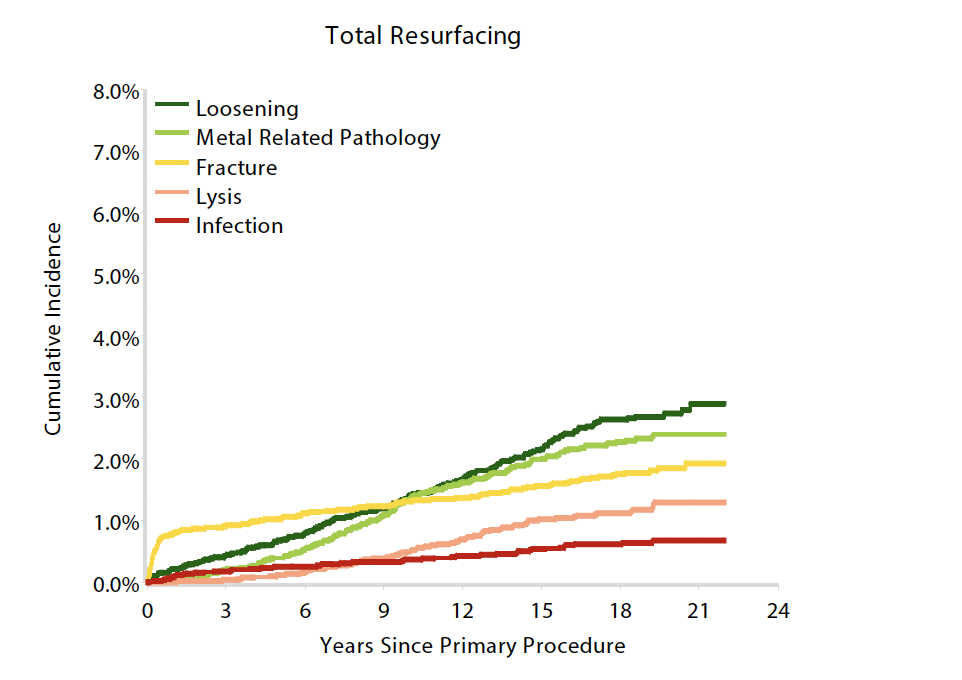

Indication for revision

Metallosis

Malloy et al JBJS Open Access 2024

- systematic review of 2,100 BHR at minimum 10 years

- 95% survival

- 20% of revisions for loosening, 20% for metal reaction

Aseptic loosening